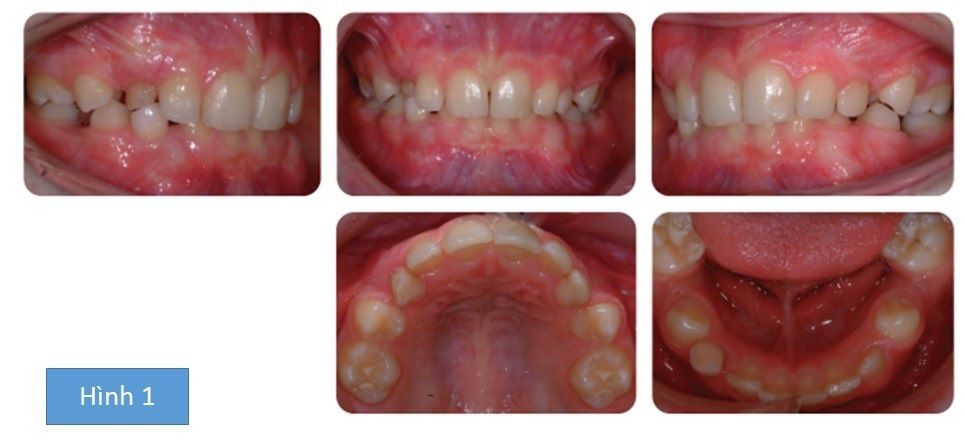

Bệnh nhân nam 10 tuổi có bộ răng hỗn hợp, có tương quan răng cửa hạng I trên kiểu xương hạng I với các kích thước dọc trung bình, phức tạp bởi:

- Các răng hàm nhỏ thứ 2 mọc ngầm ở cả 2 cung hàm trên và dưới

- Tương quan răng hàm lớn hạng II hai bên

- Cắm trùm tăng

- Các răng hàm nhỏ thứ nhất hàm dưới xoay

- R21 chết tủy